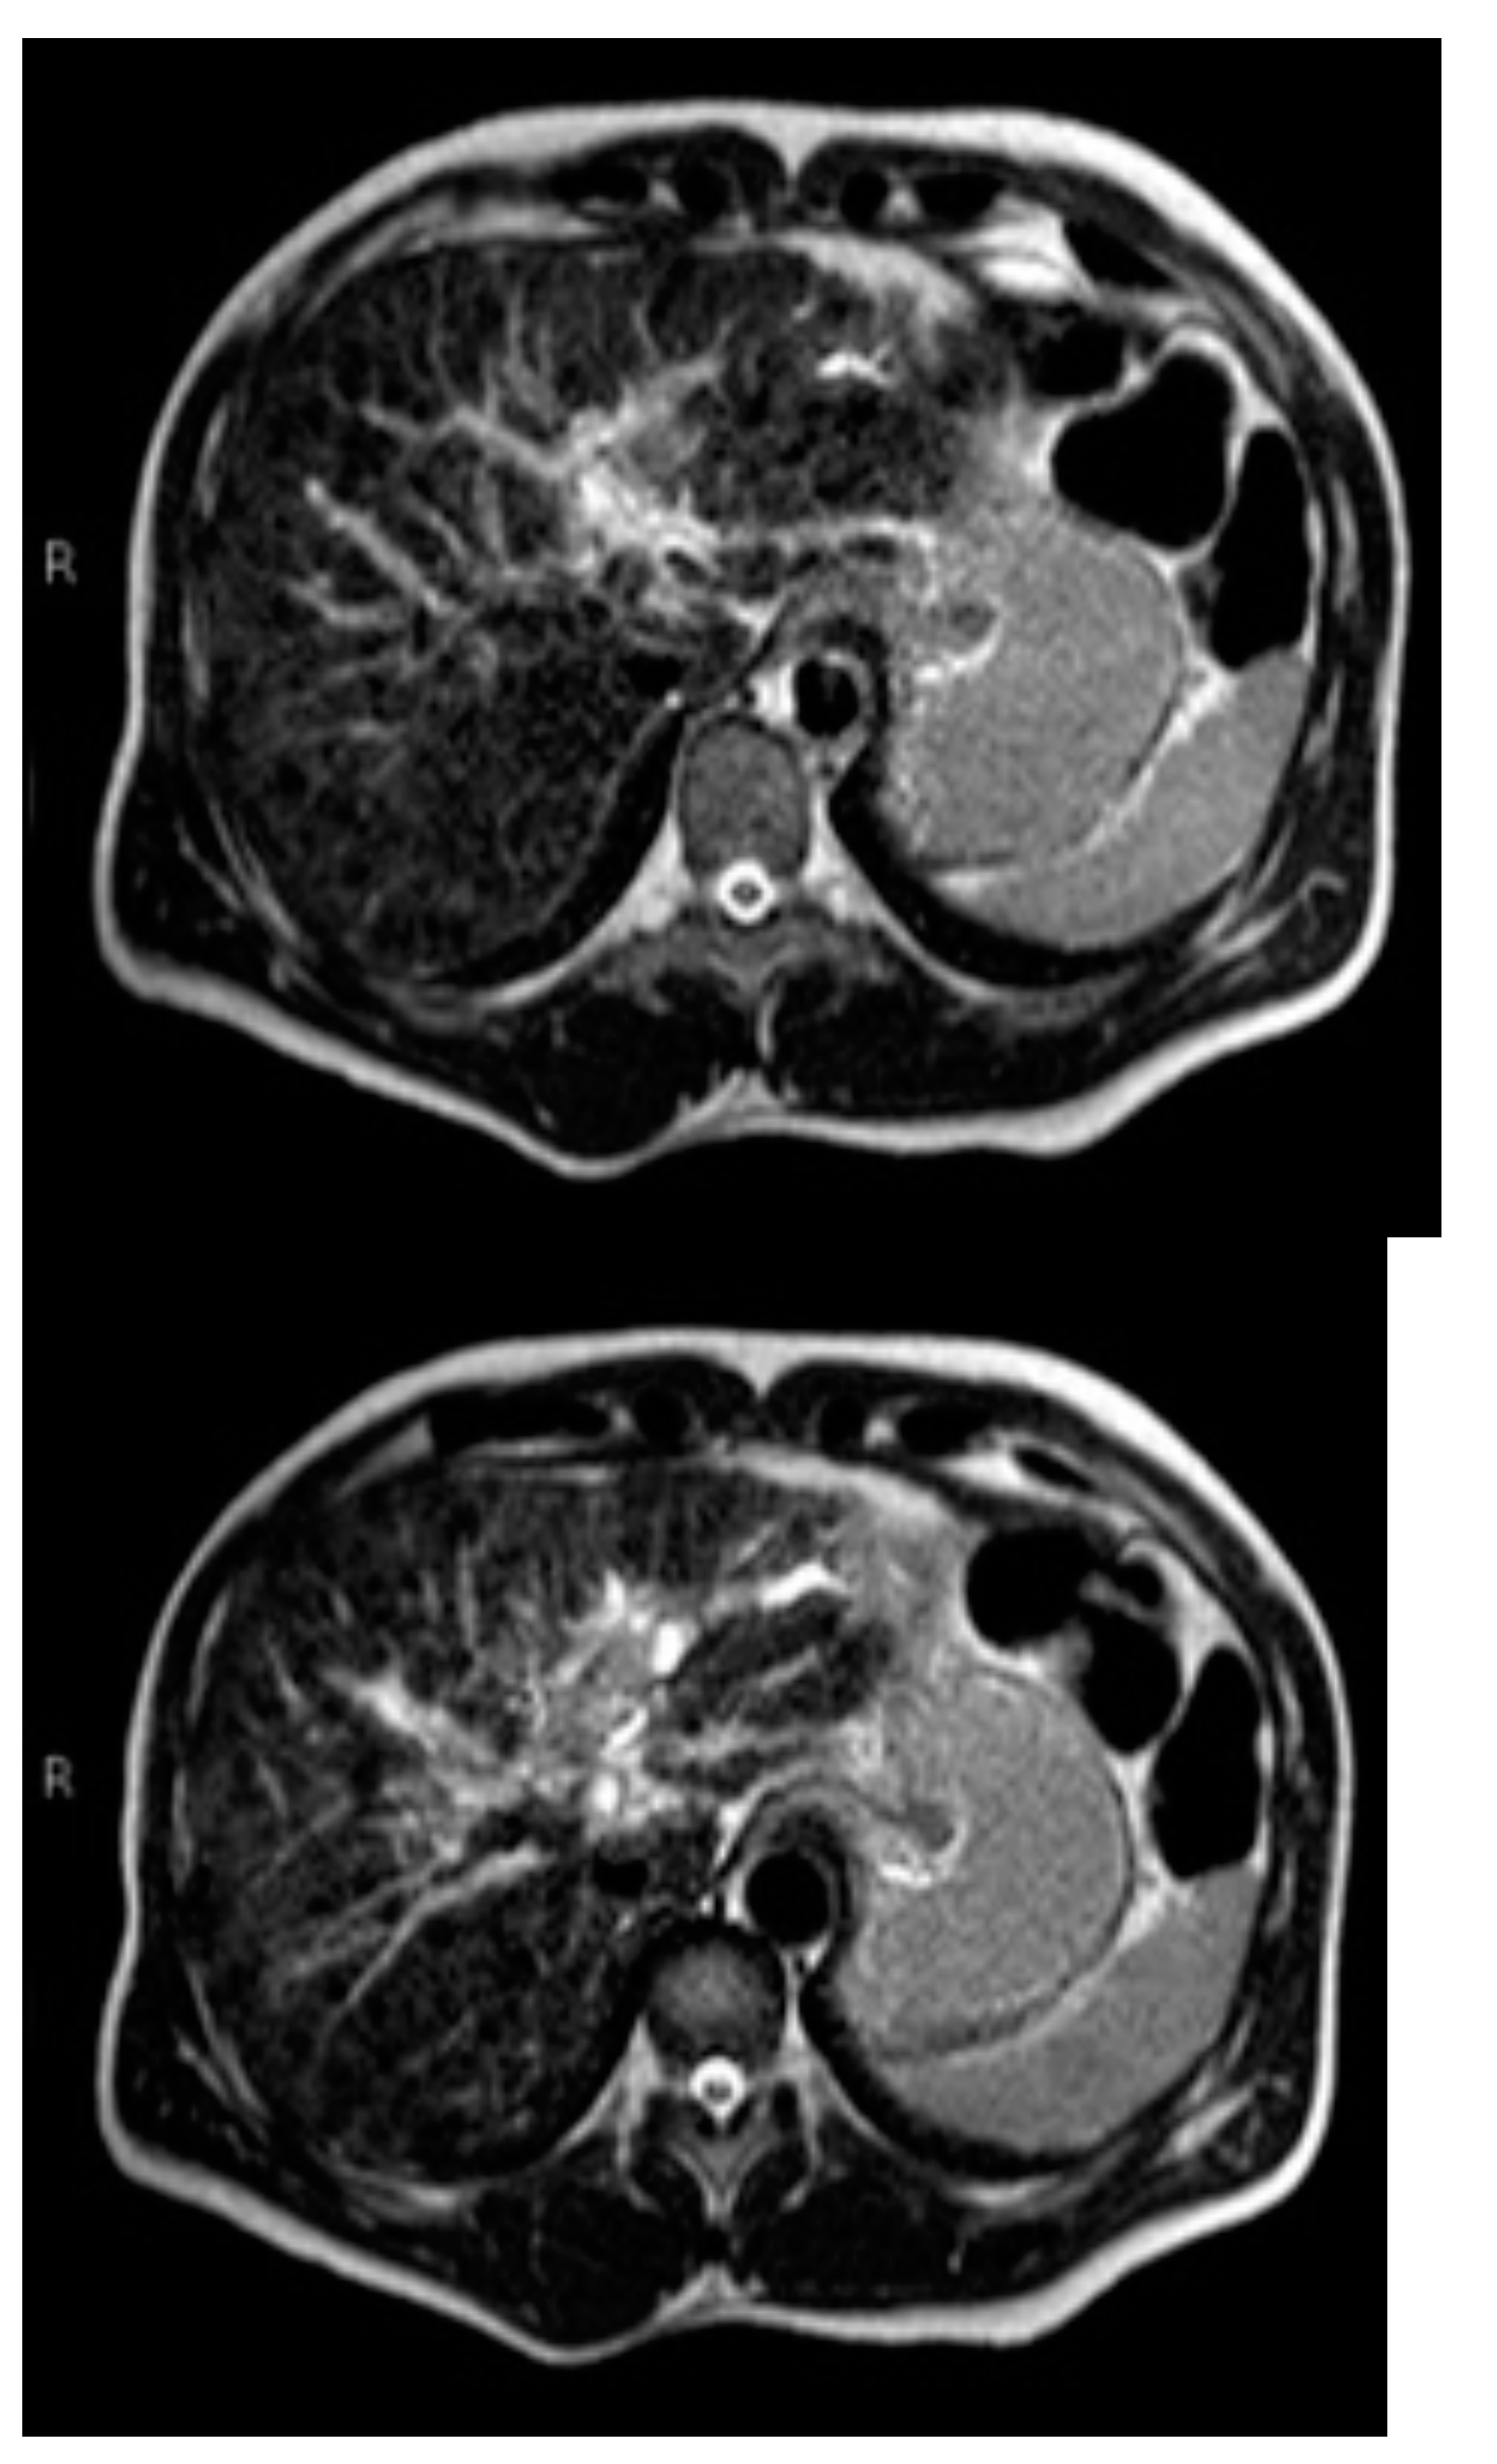

Subsequently, an upper-abdomen Computed Tomography (CT) scan and liver Magnetic Resonance Imaging (MRI) were performed (Figure 1, Figure 2, Figure 3, Figure 4, Figure 5, Figure 6 and Figure 7).

Figure 5.

MRI T2.

A mass of 1.8 cm was detected within the biliary branch for the third hepatic segment, characterized by nodular impregnation in the arterial phase and irregular and partial washout in the portal venous phase. These findings were compatible with a heterologous lesion, although it was not possible to perform a diagnosis among HCC, intrahepatic CCA or other pathological lesions.

HCC typically has an increased arterial blood supply, so it usually shows hyperattenuation in the arterial phase and hypoattenuation in the portal venous phase, compared to the hepatic parenchyma.

Most HBDTTs should show the same enhancement pattern. However, some HCCs can show iso- or hypoattenuation in the arterial phase, with the enhancement in the arterial phase inversely correlated with the degree of blood clots and necrosis. So, hypoattenuation in the portal venous phase seems to be the most important imaging feature to distinguish HCC with BDTT from perihilar CCA [17].

Washout in the portal venous phase is also the main feature to distinguish HCC with BDTT from intrahepatic CCA, together with the presence of tortuous tumoral vessels [17].